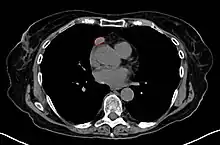

When a thymoma is suspected, a CT/CAT scan is generally performed to estimate the size and extent of the tumor, and the lesion is sampled with a CT-guided needle biopsy. Increased vascular enhancement on CT scans can be indicative of malignancy, as can be pleural deposits.[1] Limited biopsies are associated with a very small risk of pneumomediastinum or mediastinitis and an even-lower risk of damaging the heart or large blood vessels. Sometimes thymoma metastasize for instance to the abdomen.[5]